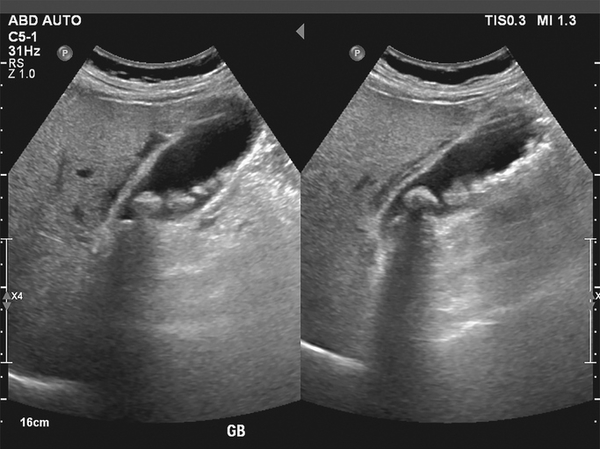

Genel Cerrahi Uzmanı Dr. Hayrettin Dizen, safra kesesi rahatsızlıklarının ihmal edildiğinde ölüme kadar götürebileceğini belirterek, "Safra kesesinde en sık rastladığımız hastalık, safra kesesi taşları. Safra kesesi taşlarını ortalama her beş kişiden birinde görüyoruz. Kırk yaşından büyük olanlarda, kadınlarda ve yüksek yağlı kolesterollü gıdayla beslenen toplumlarda safra kesesi taşları daha sık görülüyor. Bu taşlar bir şekilde safra kesesinin boşalmasını engelliyor, yani tıkıyor. Tıkandığı zaman safra kesesi iltihabı dediğimiz olay meydana geliyor. Safra kesesi iltihaplarının yüzde 95'i safra kesesi taşlarına bağlı oluşur. Bunlar taşlardan dolayı oluşan en masum durumlardır. Asıl problem, taşlar küçükse ve kanaldan safra yoluna düşerse insanlarda tıkanma sarılığı ya da kanaldaki taşın, pankreas kanalını tıkaması sonucunda akut pankreatit dediğimiz, ölümle sonuçlanabilecek rahatsızlık gerçekleşebilir. Bu yüzden safra kesesi taşı gördüğümüz olgularda, hastanın hiçbir şikayeti olmasa da ameliyat öneriyoruz" dedi.

Safra kesesi poliplerinin önemini vurgulayan Dr. Hayrettin Dizen, "Diğer bir safra kesesi hastalığımız, safra yollarında veya kesesinde polipler olabilir. Polipler de bizim için önemli. Safra kesesi polipleri safra kesesi kanserine dönüşebilir. Bu yüzden safra kesesi poliplerini gördüğümüz zaman, takip aşamasına alırız. Küçük poliplerde 6 ayda bir ultrason isteriz ama hızla büyüyorsa veya bir cm üstüne çıktıysa ameliyat öneririz. Yine burada da laparoskopik kolesistektomi dediğimiz tekniği uyguluyoruz" ifadelerini kullandı.